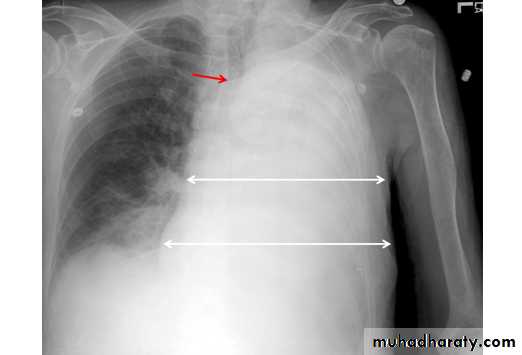

Tension pneumothorax

56.tension pneumothorax left sided aspect

57. tension pneumothorax right sided aspect